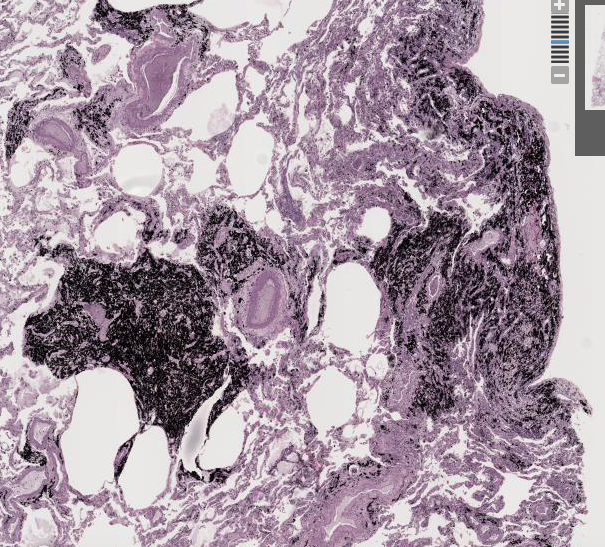

Coal miner’s lung

Anthracosis